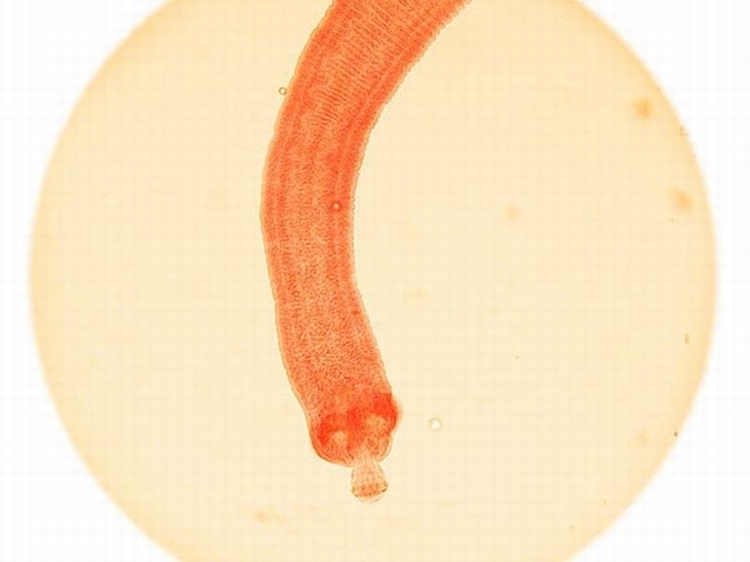

蛔虫,每年致死4500人:蛔虫会给人们带来蛔虫病,据2013年的一项研究,这种疾病每年会导致约4500人死亡。世界卫生组织称,这种感染会发生在人们的小肠内,儿童的感染率高于成年人。

绦虫,每年致死700人:绦虫是寄生虫,会给人们带来绦虫病,这种疾病每年大约导致700人死亡。